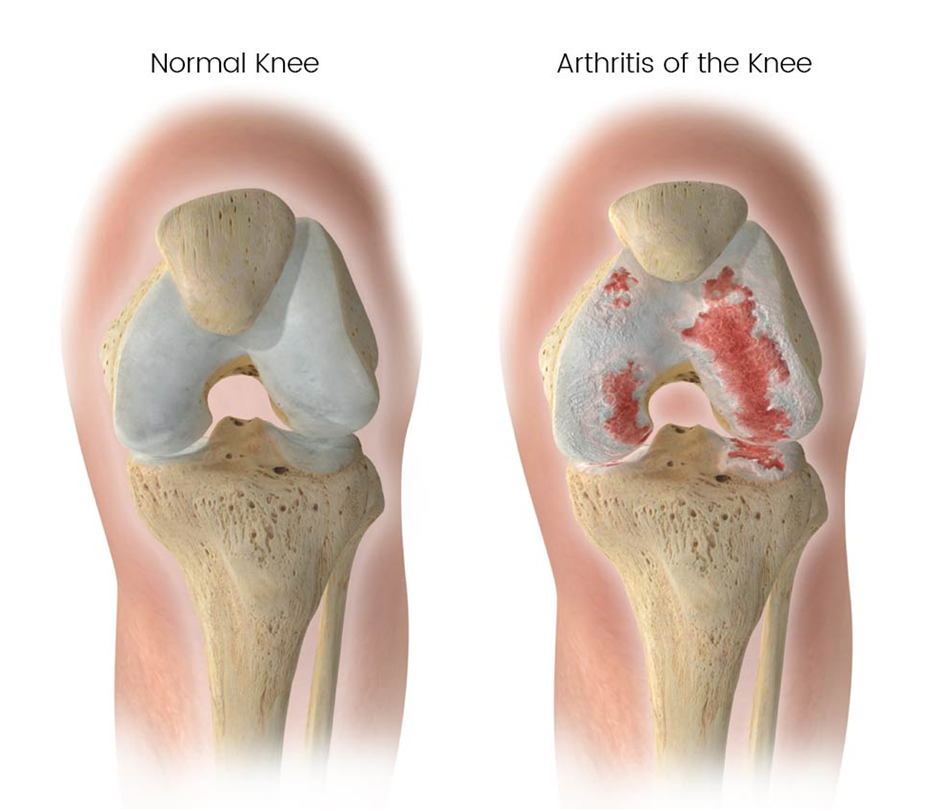

Knee replacement surgery, also known as knee arthroplasty, is a surgical procedure designed to alleviate chronic knee pain and improve joint function in individuals with severe knee damage. The surgery involves replacing the damaged or worn-out surfaces of the knee joint with artificial implants made of metal alloys, high-grade plastics, or polymers. These implants mimic the natural movement of the knee, providing stability and reducing pain.